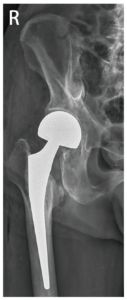

「雙極式半人工髖關節置換」手術僅需更換股骨頭,植入人工關節股骨柄,並不需要更換髖臼,復原快。這種手術的好處在於保留了髖臼的軟骨,避免了日後可能出現髖臼嚴重骨溶解的情況,同時也降低再次手術的困難度。此外,由於人工關節的置換不需要等待骨折部位癒合,患者在手術後隔天就可以使用助行器輔助行走,康復速度也更快。

手術前 手術後